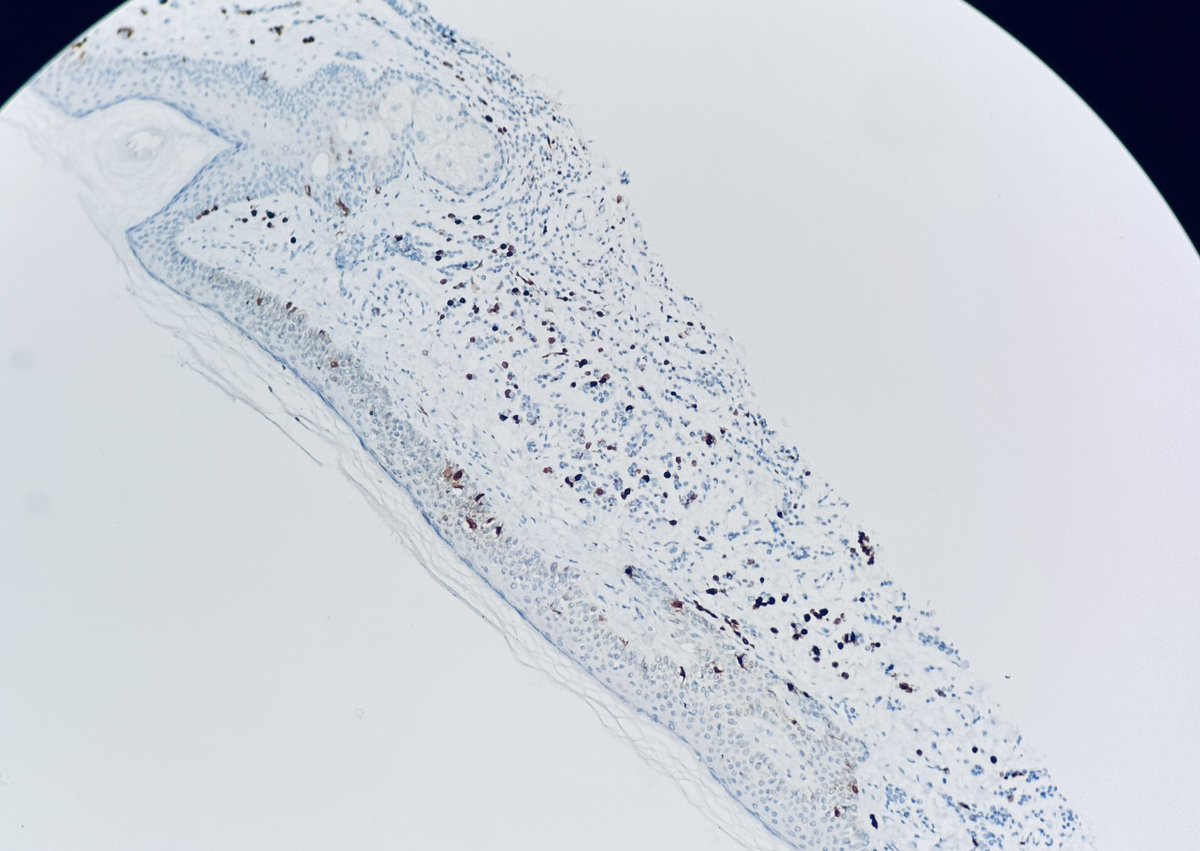

#dermpath 62 yo Man upper back. You worried about this โ€œnevusโ€ ? @david_terrano @et565 @DrGeeONE @SGottesmanMD @kis_lorand @HoustonArsenal @Dr_Jukic @glinglerimek @pembeoltulu @gonzadetoro stains are SOX10 and P16โ€ฆ